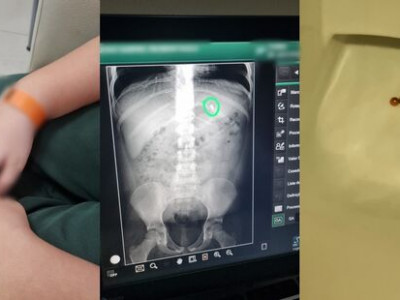

“A médica indicou um lugar para tirar raio-x para saber onde as benditas estavam e vendo que ainda se encontravam no estômago, foi uma corrida contra o tempo para retirá-las de lá. Acontece que meu filho tinha almoçado cedo, antes das 11h que é quando geralmente o almoço sai em casa e entre 13h e 14h ele comeu um pão com mortadela e tomou leite com café. Então ao chegarmos na clínica, o anestesia, disse que havia risco de broncoaspiração, então o melhor seria fazer em ambiente hospitalar, com anestesia geral e ele intubado. Pegamos as cartinhas de indicação de urgência, corremos pro hospital. A médica já estava lá para realizar o procedimento.  Infelizmente, quando ela conseguiu chegar no estômago, as bolinhas tinham descido pelo intestino. A partir daqui, a coisa ficou um 'pouco mais grave”, relembra a genitora.

“As bolinhas são de neodímio que é um ímã forte, elas estavam unidas, carne e unha, alma gêmea, bate coração. Mas com os movimentos peristálticos, poderiam separar, cada uma ir pra um lado e depois, nas alças intestinais, se reencontrarem e se reunirem, com isso perfurar o intestino, aderir na mucosa, pinçar partes dele, enfim, até causar infecção e todas essas complicações levariam ele para uma cirurgia. Fizemos ele comer bastante, dormimos no hospital. Cedo fizemos um raio-x que constatou que as bolinhas estavam no reto, só esperando a natureza chamar”, contou a mãe.